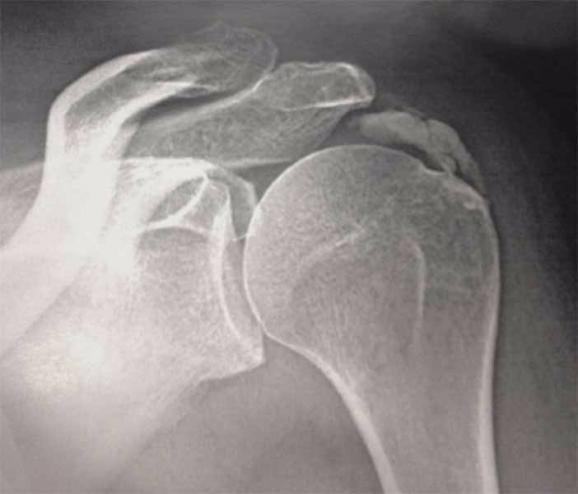

La calcification est la formation d’un amas de calcium à l’intérieur même des tendons de l’épaule, au niveau de la coiffe des rotateurs.

Le diagnostic d’une telle maladie se fait par une simple radiographie. Le traitement est dans un premier temps médical avec immobilisation du bras et prescription d’anti-inflammatoires, d’ antalgiques, puis d’infiltration et de séances de kiné.